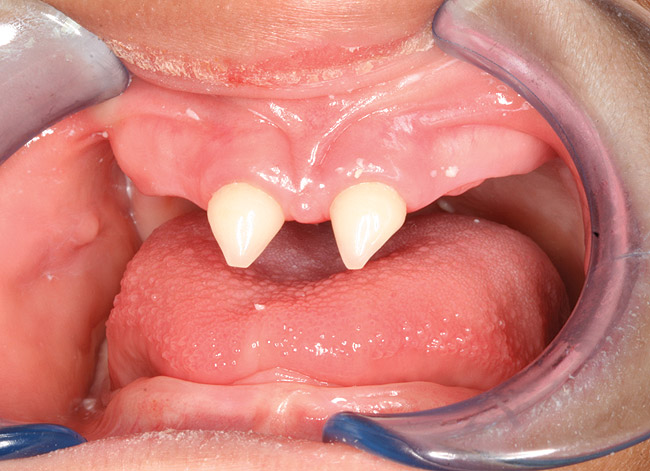

Figure 4  Pretreatment frontal view of the dental arches. Note the classic cone-shaped maxillary incisors..

Figure 4